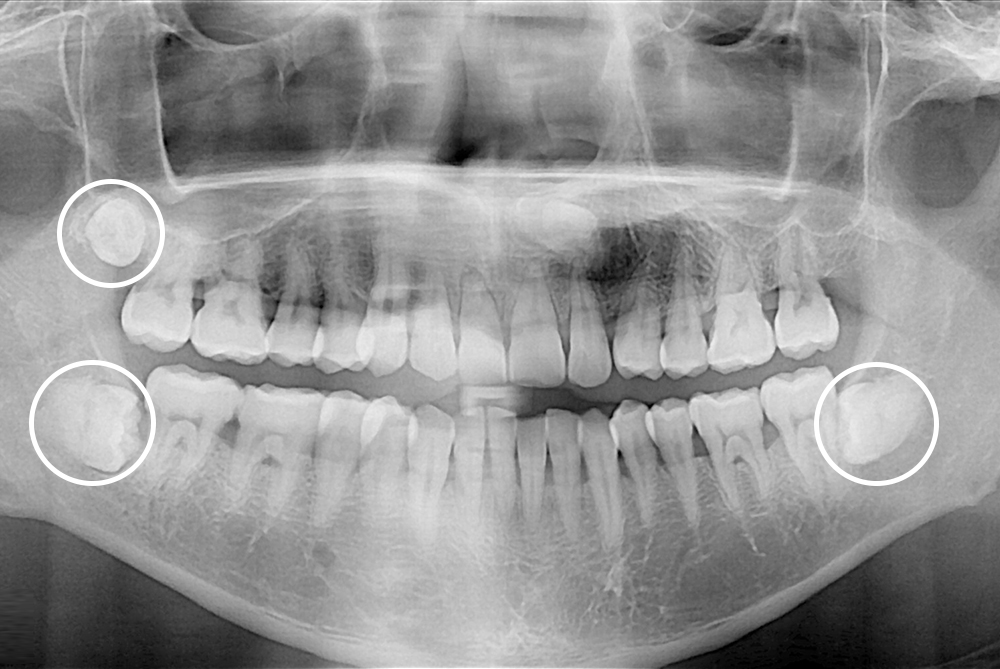

[사랑니] 매복 사랑니 발치

치료후 : 2019-04-03

세종치과는 구강악안면외과학 박사이신 원장님이 발치하는 치과입니다.